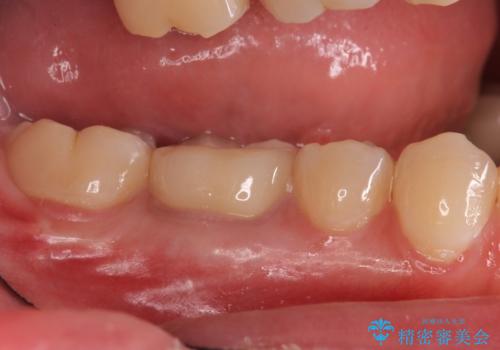

樹脂をセラミックにしたい ジルコニアクラウンでの治療

- 樹脂をやり替えたいとのことで来院されました。

特に大きな虫歯もありませんでしたが、残った歯が薄かったためクラウンでの修復処置を行いました。

- 右下6 仮歯+ジルコニアクラウン 11,000円+110,000円費用は治療当時の料金となります

インレーにすると残った歯が薄くなってしまう場合は術後の破折リスクが高いためクラウンで修復することがあります。